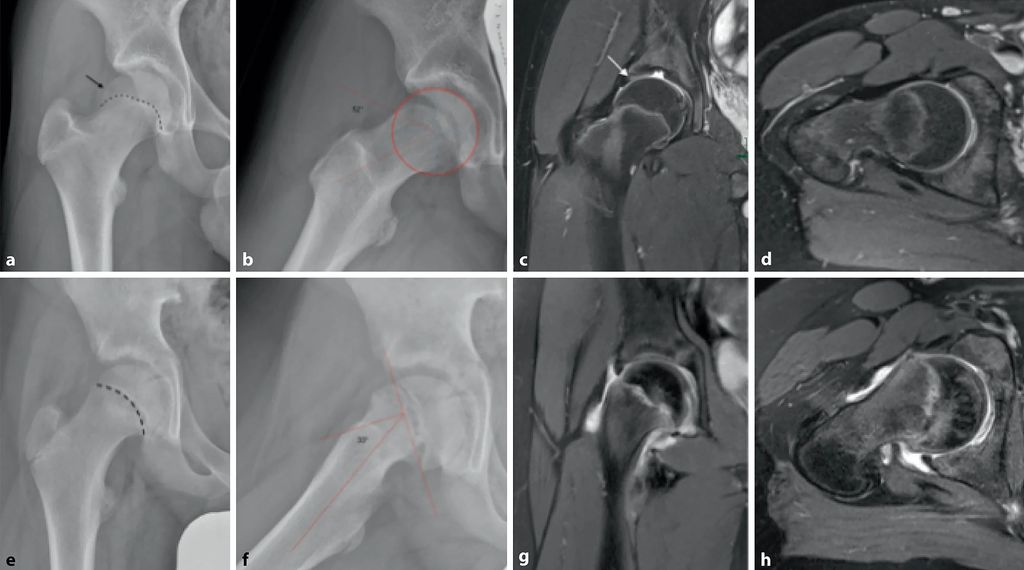

Abb. 2: a–d: Idiopathische Cam-Morphologie bei einem 14-jährigen Leistungssport-Fußballer mit trainingsassoziiertem Leistenschmerz rechts. Vorderer Impingement-Test positiv. Die Wachstumsfuge ist noch nicht verschlossen. Im anteroposterioren Projektionsröntgen (a) epiphysäre Extension (gestrichelte Linie, Pfeil). In der Dunn-View (b) zeigt sich eine Offset-Verminderung durch die inzipiente Cam-Morphologie mit einem Alpha-Winkel von 52°. Die MRT (c) zeigt eine geringe Formalteration des acetabulären Erkers sowie zumindest eine Labrumdegeneration in der chondrolabralen Transitionszone (Pfeil). Im axialen MRT (d) zeigt sich die Cam-Morphologie analog zum Röntgen. e–h: 12-jähriger Patient mit Schmerzen im Bereich des rechten Hüftgelenkes seit ca. 2 Monaten. Positives Drehmann-Zeichen mit aufgehobener Innenrotation in 90° Beugung. Im anteroposterioren Projektionsröntgen (e) findet sich eine deutlich erweiterte Physenfuge rechts. In der Lauenstein-Aufnahme (f) findet sich mit einem Southwick-Winkel von 33° eine moderat abgeglittene Epiphyse, die zu einer sekundären Cam-Morphologie führt; in der MRT (g, h) ist das Ausmaß dreidimensional bestimmbar; zudem zeigt sich ein Knochenmarködem (aus Chiari et al. 2022)5